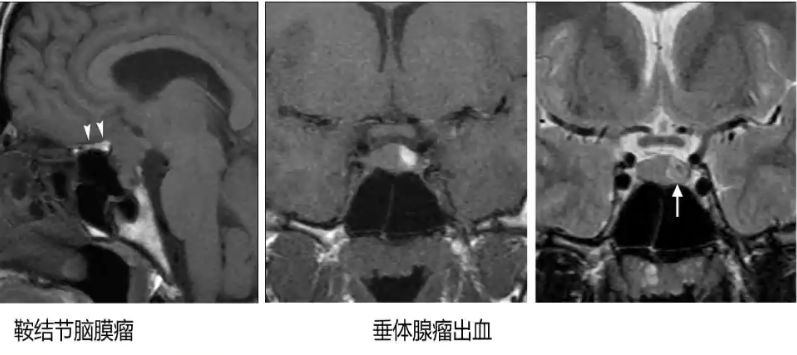

2. 病理状态:血凝块(垂体瘤出血、垂体卒中、sheehan综合征或动脉瘤血栓形成);高蛋白成份(Rathke’s囊肿、颅咽管瘤及粘液囊肿);脂肪(脂肪瘤、皮样囊肿、脂样脑膜瘤);钙化(颅咽管瘤、软骨瘤、脊索瘤);顺磁性物质(锰、黑色素)